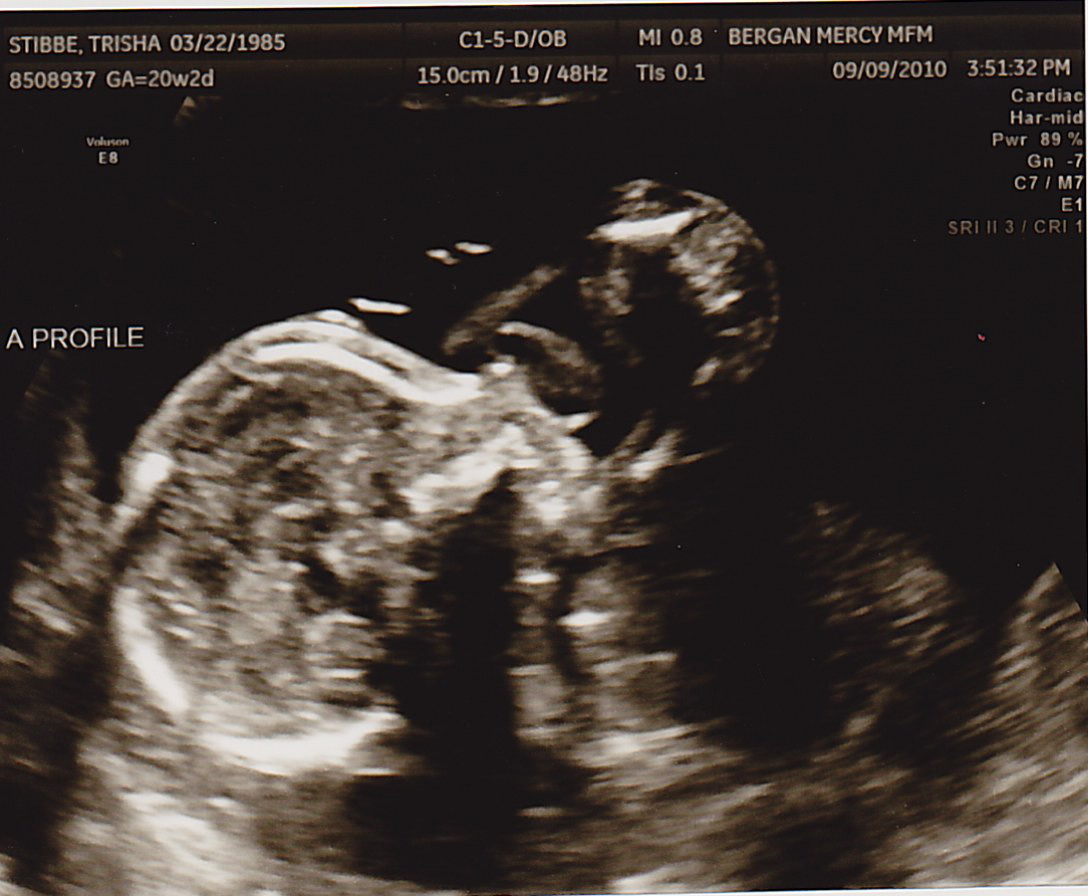

Another successful appointment! The fluid around Baby B is looking really good. No procedures today. Whew! Those little boys are fighters 🙂